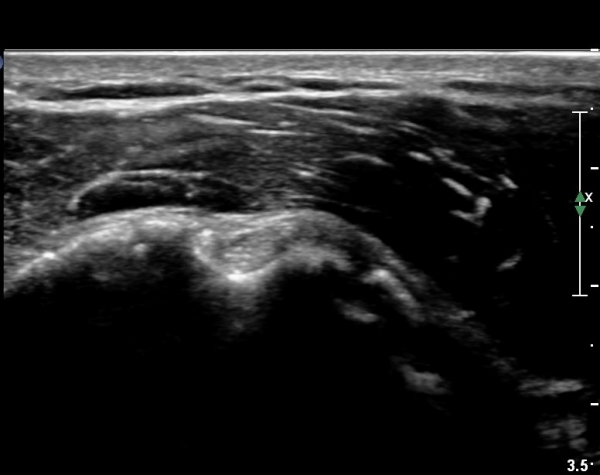

°ß°©ÇÏ±Ù°Ç È¾´Ü¸é°Ë»ç»ó ¼Ò°áÀý ÇÊÁú°ñº¯È­¿Í °ß°©ÇÏ±Ù°Ç Áߺο¡ °í¿¡ÄÚ µ¢¾î¸®°¡ °üÂûµÇ°í

¼®È¸ À§ÂÊ(¸Ó¸®ÂÊ)ÀÇ ÈûÁÙÀÇ Àú¿¡ÄÚ º¯È­°¡ °üÂûµÈ´Ù(»çÁø 4, 5).